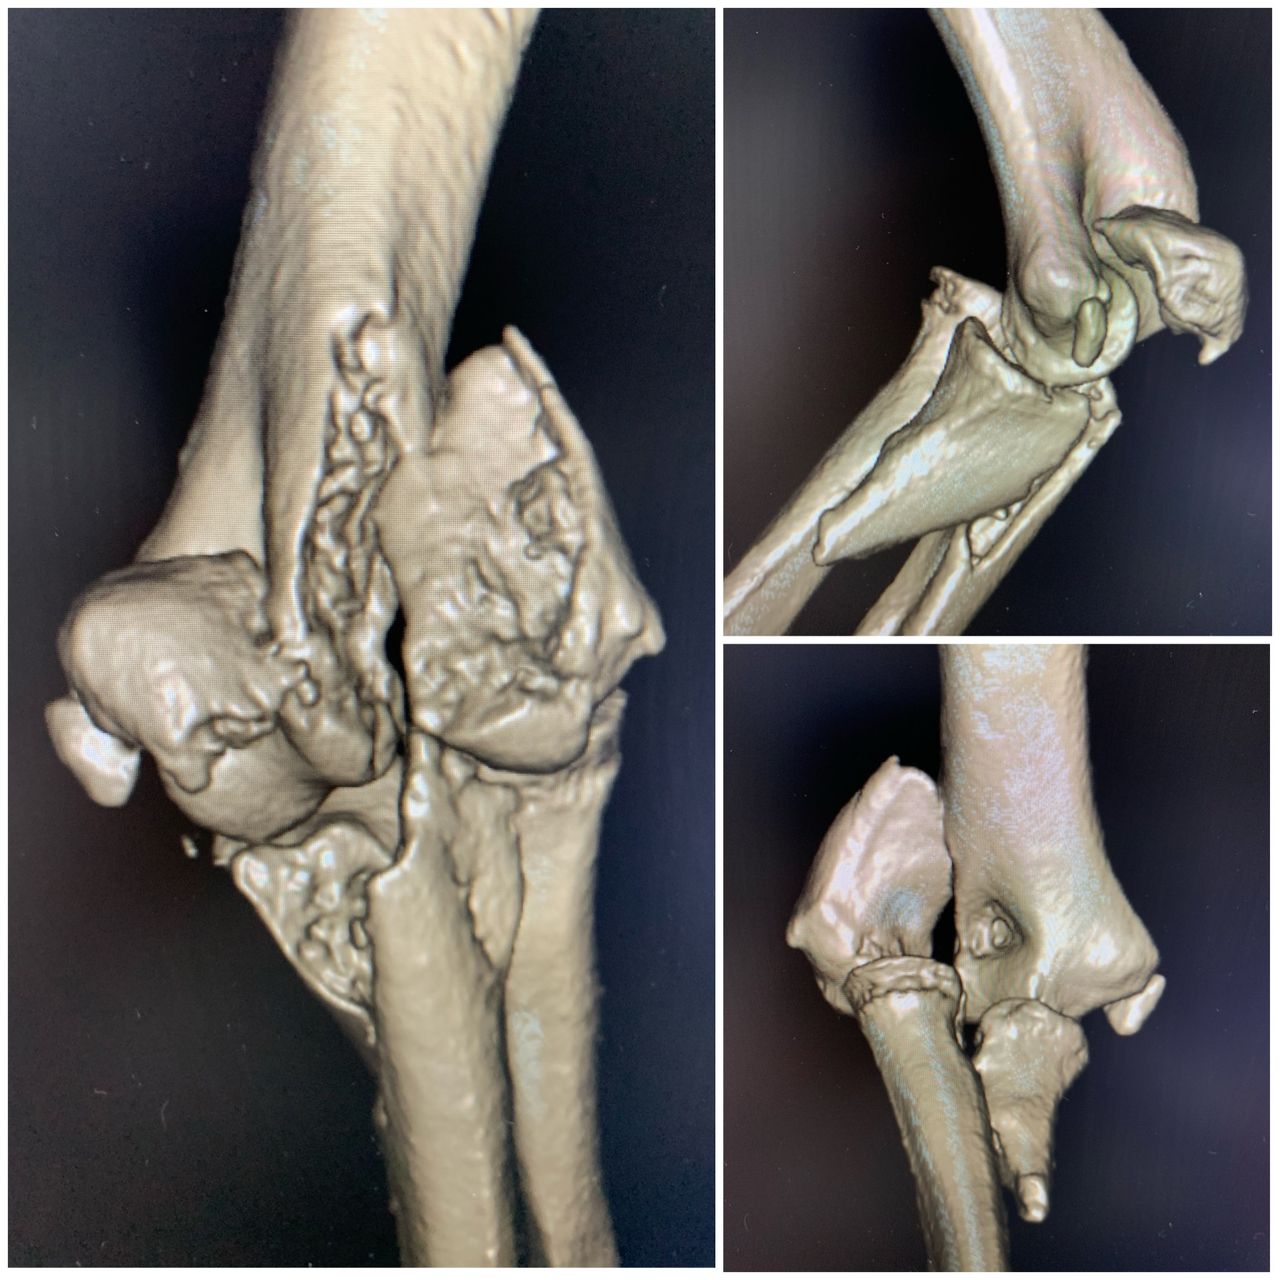

Se especializa en Síndrome del Manguito Rotador, Artroscopía de Hombro, Luxación de Hombro, Epicondilitis Lateral (Codo de Tenista), Fractura de Clavícula, Disyunción Acromioclavicular, Fracturas de Codo.

Conferencista. Tríada Terrible del Codo. II Jornadas de Traumatología. Hospital Universitario de Caracas (HUC). Caracas, Venezuela. 2015